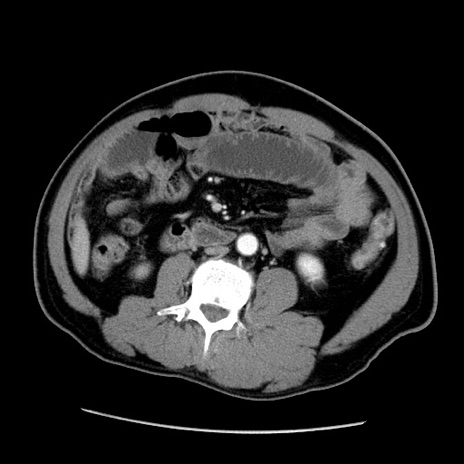

症例22(横断像)

【症例】50歳代男性

【主訴】腹痛

【現病歴】AVMからの被殻出血のため回復期リハ病棟入院中。 本日午後3時頃急に下腹部痛が出現した。

【既往歴】AVM、被殻出血、虫垂炎、高血圧

【身体所見】意識晴明、左半身不全麻痺、会話の理解は良好、36.5°C、腹部:膨隆、全体に板状硬、下腹部正中に圧痛点あり、反跳痛-、筋性防御不明、右下腹部にope scar

【データ】WBC 9400、CRP 0.06